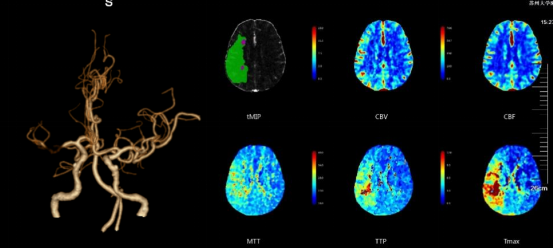

患者为一名65岁男性,3月16日突发左侧肢体活动障碍,次日症状加重,并出现反应迟钝、言语不清、口角歪斜等新发症状后转至苏大附四院继续治疗。入院后CTA(CT血管造影术)检查提示右侧大脑中动脉水平段(R-M1)管腔完全闭塞,远段分支稀疏;CTP(脑灌注检查)则提示右侧额顶颞叶缺血性灌注异常;头颅MRI(核磁共振成像)见右侧岛叶、颞叶、右侧脑室旁及放射冠区急性脑梗死。综合检查结果,考虑到患者发病时间较长,与家属商议后予以强化内科治疗。

CTA+CTP:右侧大脑中动脉水平段(R-M1)管腔完全闭塞;右侧额顶颞叶缺血性灌注异常

患者再次入院后,郝永岗教授等专家合作完成苏州市首例术中磁共振指导下的症状性颅内动脉狭窄支架植入术。此次手术充分利用我院复合手术室(DSA+MRI双杂交)的优势,有效提高了手术的安全性和有效性。术后即刻行MRI-PWI显示:责任血管供血区血流灌注较前明显改善,提示支架精准定位释放。

术前PWI:右侧岛叶、颞叶、右侧脑室旁及放射冠区CBF、CBV减低,MTT、TTP较对侧延长

术后PWI:右侧岛叶、颞叶、右侧脑室旁及放射冠区血流明显改善